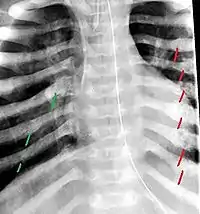

The material factual allegations of the amended complaint are as follows. Plaintiff was born on May 14, 1970. On repeated occasions during the first year of her life she was severely beaten by her mother and the latter's common law husband, one Reyes. On April 26, 1971, when the plaintiff was eleven months old, her mother took her to the San Jose Hospital for examination, diagnosis, and treatment. The attending physician was defendant Dr. Flood, acting on his own behalf and as agent of the defendant San Jose Hospital. At the time, the plaintiff was suffering from a comminuted spiral fracture of the right tibia and fibula, which gave the appearance of having been caused by a twisting force. Plaintiff's mother had no explanation for this injury. Plaintiff had bruises over her entire body. In addition, she had a non-depressed linear skull fracture which was then in the process of healing. Plaintiff demonstrated fear and apprehension when approached. Inasmuch as all plaintiff's injuries gave the appearance of having been intentionally inflicted by other persons, she exhibited the medical condition known as the battered child syndrome.

It is alleged that proper diagnosis of plaintiff's condition would have included taking X-rays of her entire skeletal structure, and that such procedure would have revealed the fracture of her skull. Defendants negligently failed to take such X-rays, and thereby negligently failed to diagnose her true condition. It is further alleged that proper medical treatment of plaintiff's battered child syndrome would have included reporting her injuries to local law enforcement authorities or juvenile probation department. Such a report would have resulted in an investigation by the concerned agencies, followed by a placement of plaintiff in protective custody until her safety was assured. Defendants negligently failed to make such report.

The complaint avers that as a proximate result of the foregoing negligence plaintiff was released from the San Jose Hospital without proper diagnosis and treatment of her battered child syndrome, and was returned to the custody of her mother and Reyes who resumed physically abusing her until she sustained traumatic blows to her right eye and back, puncture wounds over her left lower leg and across her back, severe bites on her face, and second and third degree burns on her left hand.

On July 1, 1971, plaintiff was again brought in for medical care, but to a different doctor and hospital. Her battered child syndrome was immediately diagnosed and reported to local police and juvenile probation authorities, and she was taken into protective custody. Following hospitalization and surgery she was placed with foster parents, and the latter subsequently undertook proceedings to adopt her. Plaintiff's mother and Reyes fled the state, but were apprehended, returned for trial, and convicted of the crime of child abuse.[3]

While helpful, the foregoing general history of the battered child syndrome is not conclusive on the precise question in the case at bar. The question is whether a reasonably prudent physician examining this plaintiff in 1971 would have been led to suspect she was a victim of the battered child syndrome from the particular injuries and circumstances presented to him, would have confirmed that diagnosis by ordering X-rays of her entire skeleton, and would have promptly reported his findings to appropriate authorities to prevent a recurrence of the injuries. There are numerous recommendations to follow each of these diagnostic and treatment procedures in the medical literature cited above.

For example, the leading article by Kempe et al., op. cit., supra,[10] states that "A physician needs to have a high initial level of suspicion of the diagnosis of the battered-child syndrome in instances of subdural hematoma, multiple unexplained fractures at different stages of healing, failure to thrive, when soft tissue swelling or skin bruising are present, or in any other situation where the degree and type of injury is at variance with the history given regarding its occurrence . . . ." (Id., at p. 20.) Of the different types of fractures exhibited, an arm or leg fracture caused by a twisting force is particularly significant because "The extremities are the 'handles' for rough handling" of the child by adults. (Id., at p. 22.) The article also contains numerous recommendations to conduct a "radiologic examination of the entire skeleton" for the purpose of confirming the diagnosis, explaining that "To the informed physician, the bones tell a story the child is too young or too frightened to tell." (Id., at p. 18.) Finally, on the subject of management of the case it is repeatedly emphasized that the physician "should report possible willful trauma to the police department or any special children's protective service that operates in his community" (id., at p. 23) in order to forestall further injury to the child: "All too often, despite the apparent cooperativeness of the parents and their apparent desire to have the child with them, the child returns to his home only to be assaulted again and suffer permanent brain damage or death." (Id., at p. 24.)